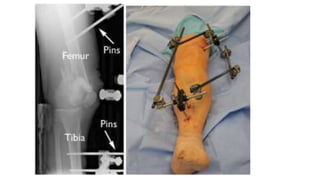

1) EXTERNAL FIXATION

• In this type of operation, metal pins or screws are placed into the

middle of the femur and tibia (shinbone). The pins and screws are

attached to a bar outside the skin. This device is a stabilizing frame

that holds the bones in the proper position until you are ready for

• Precaution avoid pin placement in area of planned plate placement if

1) EXTERNAL FIXATION •Temporizing measure until soft tissues permit internal fixation, or until patient is stable • In this type of operation, metal pins or screws are placed into the middle of the femur and tibia (shinbone). The pins and screws are attached to a bar outside the skin. This device is a stabilizing frame that holds the bones in the proper position until you are ready for surgery. • Precaution avoid pin placement in area of planned plate placement if possible